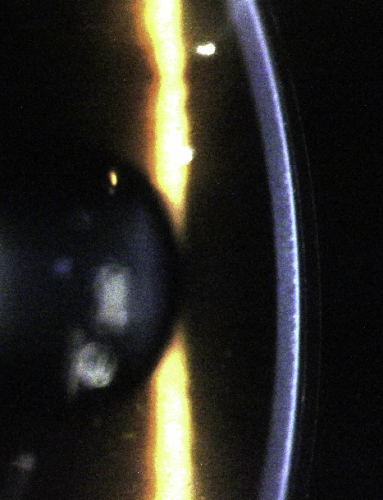

Cue the deafening sounds of aghastment. Fitting an already heathen device to a previously altered cornea? You must be mad! Indeed, in the main orthokeratology ‘bible’; John Mountford’s Orthokeratology: Principles and Practice published back in 2004, there is no mention of fitting orthoK to the post-LASIK cornea (although John is working on a new edition which may address this). A pubmed search shows no articles about orthoK on a post-LASIK cornea. Despite this many experienced orthokeratologists around the world practice ortho-K on the post-LASIK cornea with excellent results. I personally believe there is no more harm in fitting orthokeratology lenses to a lasered cornea than to a virgin example. It is the understanding of most orthokeratologists that the refractive effect of orthoK comes about due to modification of the epithelial cells of the cornea, although the jury is still out in some circles. The following OCT of a patient of mine using orthoK lenses for high myopia illustrates this by showing the thinned epithelium centrally and thickened layer para-centrally. The stroma remains relatively uniform. In contrast all forms of laser refractive corneal surgery involve permanent modification to the stroma of the cornea. The mechanism of refractive change in these two modalities are mutually exclusive. In post-LASIK orthoK the main challenge comes with designing the back surface of an orthokeratology lens to firstly fit the para-central cornea safely and comfortably, and secondly remodel the central epithelium in a way to correct the refractive error. Let’s look at an example:

Anterior OCT showing the thickness profile of the corneal epithelium in myopic orthokeratology. Note this well-fitted lens does not touch the cornea within the treatment zone.